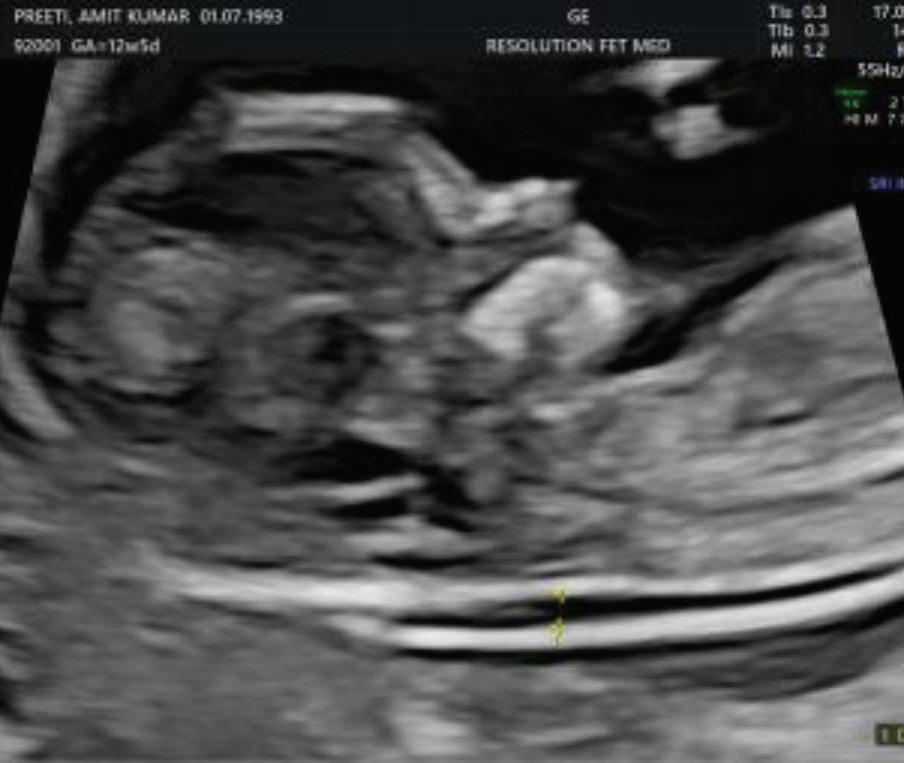

2. NUCHAL TRANSLUCENCY (NT) SCAN

• Done @11–13+6 weeks.

• CRL 45–84 mm.

• This is the cornerstone of first trimester screening.

MEASUREMENTS THAT CAN BE OBTAINED ON

First Trimester Fetal Evaluation:

FETAL ULTRASOUND EXAMINATION AT 11 TO 14 + 0 WEEKS: BASIC BIOMETRY INCLUDES:

Nuchal Translucency

Biperital Diameter

(a) Crown Rump Length(CRL)

(b) Biperital diameter(BPD)

(c) Nuchal Translucency(NT)

DETAILED BIOMETRY INCLUDES:

Along with basic biometry

(a) Abdominal circumference

(b) Head circumference

(c) Femur length

Abdominal Circumference

1. NT is the sonographic appearance of subcutaneous accumulation of fluid behind the fetal neck, below the skin in the first trimester of pregnancy.

2. Measured in mid-saggital section only.

3. Measured between 11-14 weeks.

4. CRL between 45-84mm.

5. Magnified to include only head and upper thorax.

6. Fetus should be in neutral position.

7. Demostrate fetus separate from amnion.

8. Measurement should be ON to ON (cross bar of the callipers should be such that it’s hardly visible and merges with white line, not nuchal fluid).

During the scan more than one measurement should be taken and maximum value should be considered.